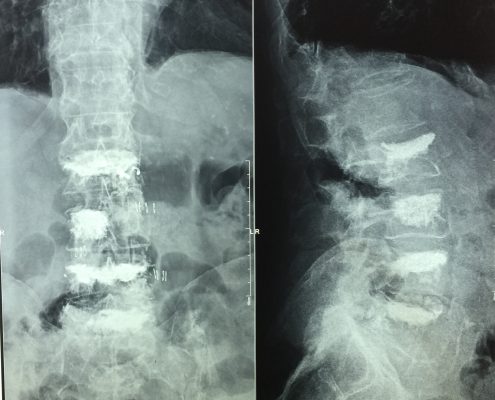

El sistema SpineJack® ha sido diseñado para la reducción anatómica de Fracturas Vertebrales por Compresión (FVC de tipo A1, A2 y A3 según la clasificación de Magerl), con o sin patologías subyacentes que afecten a la calidad del hueso, como la osteoporosis y las lesiones de origen oncológico (metástasis osteolítica o mieloma).

El médico realiza dos incisiones muy finas, aproximadamente de 1 cm de longitud, en la espalda, y crea una estrecha vía de acceso a la vértebra fracturada para insertar dos implantes.

Seguidamente, el médico introduce los implantes e inyecta el cemento óseo que estabilizará la fractura.